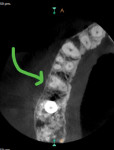

The clinical examination revealed severe pain to percussion and biting as well as vitality testing showing tooth No. 4 to have a necrotic pulp. Periodontal examination produced no pathologic pocketing or mobility. Upon examination of the digital radiograph in the region of the patient's pain, a periapical radiolucency was found associated with tooth No. 4 (Figure 1). A cone-beam computed tomography (CBCT) scan also confirmed the periapical pathology, as well as tooth No. 4 exhibiting three roots/canals (Figure 2 and Figure 3).